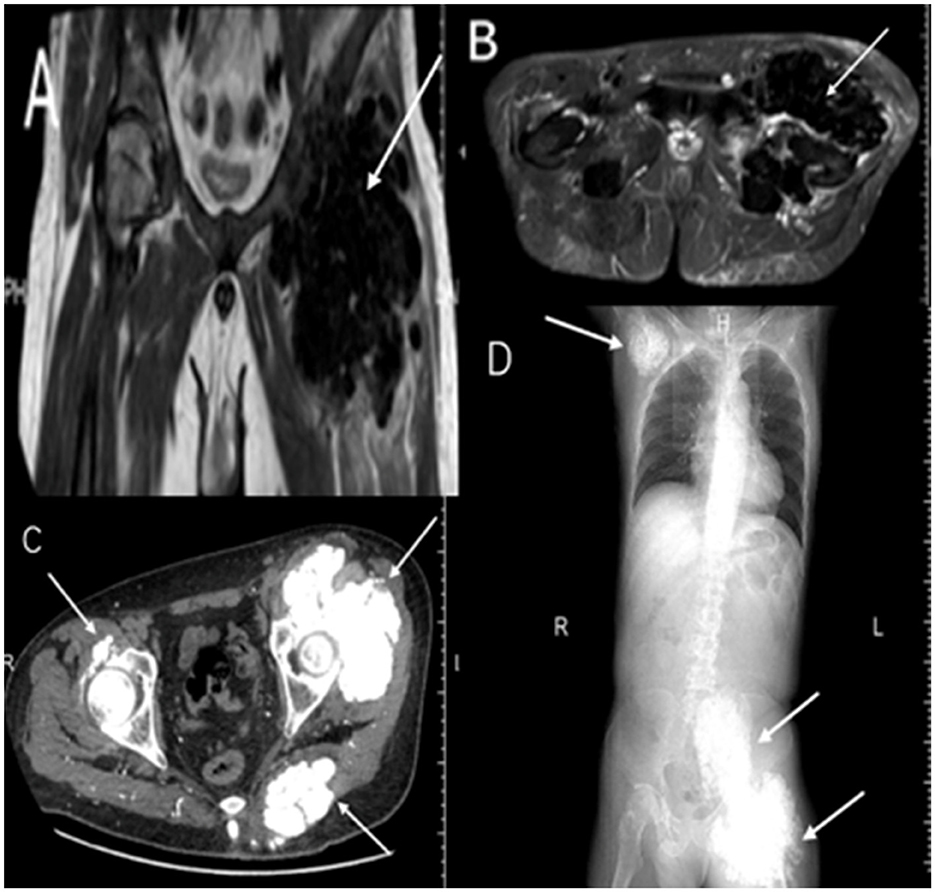

Eighteen months after thyroid surgery, follow-up imaging revealed new extensive metastatic calcifications involving the shoulders, ribs, spine, femur, and sacrum (Figures 1C, D). In March 2023, the patient presented with worsening bilateral ankle ulcers, including a 15 cm stellate calciphylactic skin lesion (Figure 2A). Wound secretion cultures were negative, ruling out necrotizing soft tissue infection. Inflammatory markers were significantly elevated: white blood cell count 11.62 × 109/L, high-sensitivity CRP 279.88 mg/L, PCT 14.88 ng/ml, and persistent hyperphosphatemia (serum phosphorus 2.19 mmol/L). Given the severity of his condition, the patient started intravenous STS therapy on March 29, 2023, following a stepwise dose-escalation protocol: starting at 3.5 g daily, increasing every other day to 5, 7, 8 g, and ultimately 10 g daily. The patient completed a 2-week course of treatment. In addition to STS, the patient received piperacillin-tazobactam for infection, Dan Shen injection for microcirculatory improvement, sevelamer for phosphorus control, esomeprazole for gastric protection, and optimized dialysis (using low-calcium dialysate). After the first STS course, CRP decreased by 77.3% (from 279.88 to 63.63 mg/L), and the ulcer area reduced by 42% (Figure 2B).

Figure 2

Cutaneous manifestations pre- and post-sodium thiosulfate (STS) therapy. (A) Pretreatment stellate ulcer (15 cm) with characteristic eschar at medial malleolus. (B) Significant wound reduction after initial STS course. (C, D) Complete epithelialization following second STS cycle.

A second course of STS therapy was started on May 12, 2023, with a dose escalation from 5 g daily to 6, 8, and 10 g, maintained for 1 week, completing a total of 2 weeks. This resulted in complete epithelialization of the ulcer (Figures 2C, D), and no adverse events, such as gastrointestinal reactions, hypotension (BP 130–170/75–100 mmHg), acidosis, allergic reactions, or QTc prolongation, were observed. However, despite improvement in the skin lesions, imaging showed gradual calcification in the knee region, indicating the ongoing progression of deep tissue calcification (Figures 3A–C). The patient was subsequently transferred to another dialysis center, and follow-up by phone confirmed that the patient's lower extremity ulcers had not recurred and no new lesions had developed at other sites.